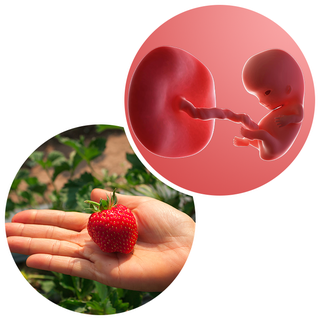

What does my baby look like?

Your baby, or foetus, is now around 22mm long from head to bottom, which is about the size of a strawberry.